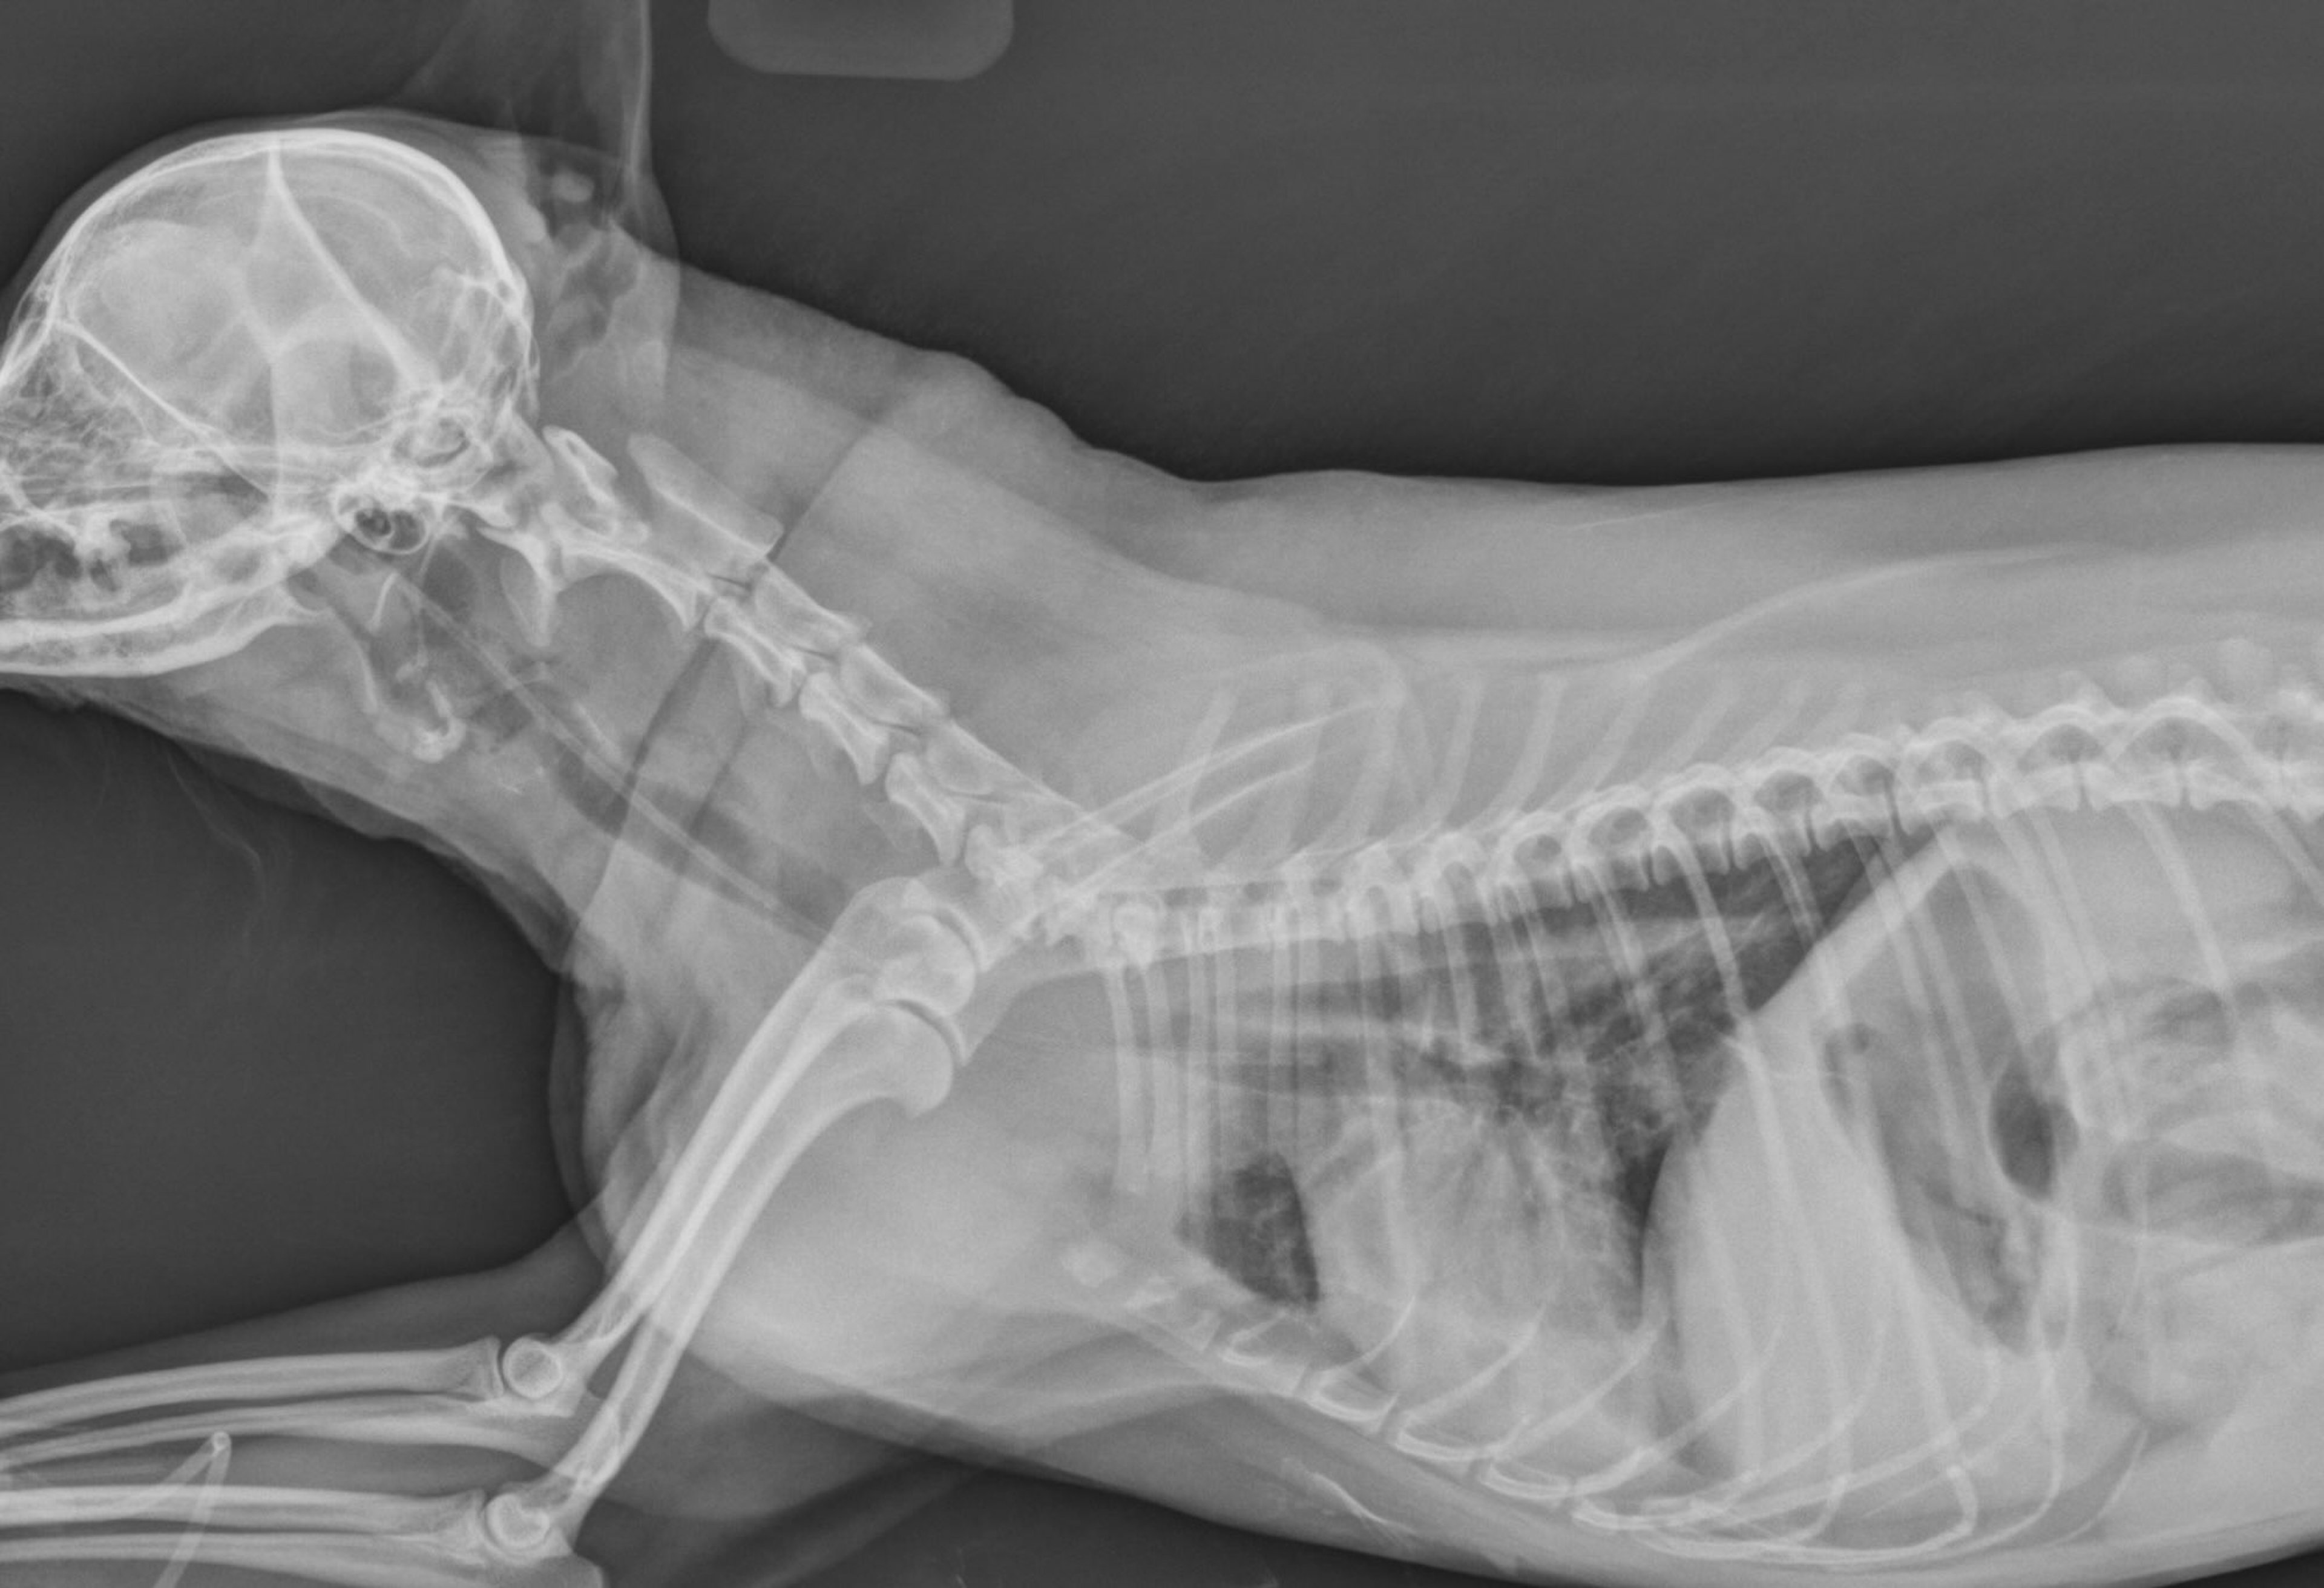

• head trauma (see image of puppy with head trauma)